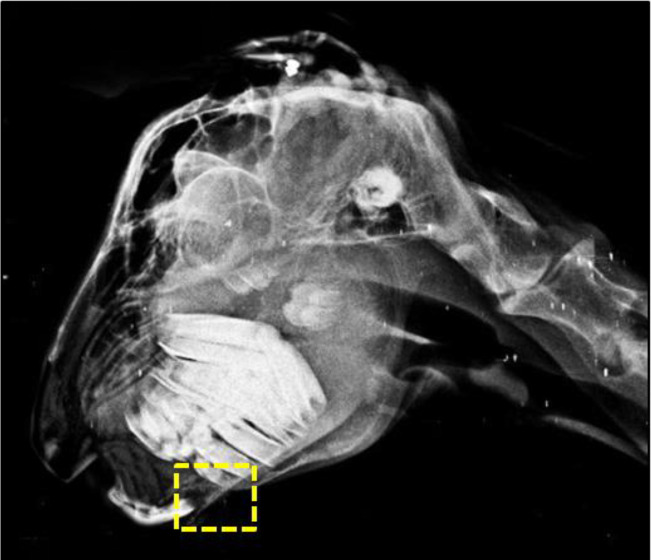

Findings/treatment and outcome: The clinical examination revealed bilateral mandibular enlargement and limb deformities. On radiography, the maxilla and mandible had decreased radiopacity. Fine needle aspiration cytology (FNAC) from the affected bones showed occasional fibroblasts and individual osteoclasts clusters. On necropsy, the enlarged mandible revealed a meaty consistency. Undecalcified histological sections of the mandible showed severe osteopenia, multiple osteoclasts, Howship's lacunae, and extensive fibroplasia. Dietary corrective measures led to the prevention of ODF in the rest of the flock.